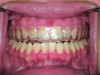

(3.) Intraoral facial and occlusal views, respectively, of the completed boil-and-bite sports mouth guard.

Figure 3

(4.) Intraoral facial and occlusal views, respectively, of the completed boil-and-bite sports mouth guard.

Figure 4